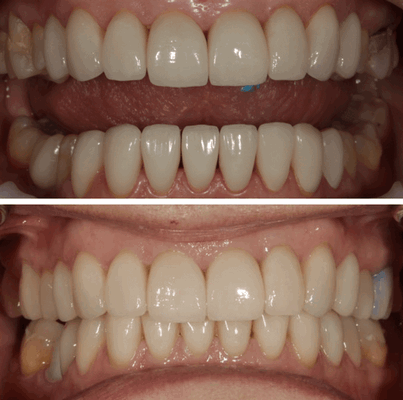

Итак, улыбка при заболевании ВНЧС - ДО и ПОСЛЕ

Как говорится - почувствуйте разницу. А самое главное - что лечение височно нижнечелюстного сустава на фоне исправления прикуса и формирования красивой улыбки прошло отлично. Сейчас нагрузки на ВНЧС в пределах нормы, он не перегружен и идет процесс его восстановления.

Устранены все жалобы (отсутствуют болевые ощущения, хруст, щелчки в височно нижнечелюстном суставе суставе). Хотя сами щелчки не всегда устранимы при застарелой патологии, но в данном случае нам удалось полностью исключить патологический щелчок ВНЧС .

Сроки лечения данной пациентки, ортодонтическая подготовка заняла около 7 месяцев (ношение элайнеров), на этапе ортодонтической реабилитации проведён этап хирургической реабилитации (установка имплантата в области 46-го зуба), окончательная ортопедическая реабилитация заняла ещё 2 месяца .

Итого мы получили 9-10 месяцев лечения